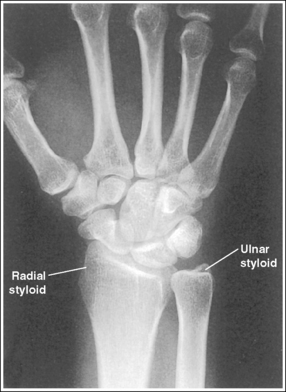

See Figure 4-36 and Box 4-13.

Contrast and density are adequate to demonstrate the pronator fat stripe and surrounding posterior wrist soft tissue.

• The pronator fat stripe is one of the soft tissue structures that should be demonstrated on all lateral wrist projections (Figure 4-37). It is located parallel to the anterior (volar) surface of the distal radius, is normally convex, and lies within 0.25 inch (0.6 cm) of the radial cortex. Bowing or obliteration of this fat stripe may be the only indication of a subtle radial fracture.

• The soft tissue that surrounds the posterior (dorsal) aspect of the wrist should also be visible. This posterior soft tissue is convex on the uninjured wrist. To the reviewer, a straightening or concave appearance of this surface may indicate swelling and injury.

The wrist is in a lateral projection. The anterior aspect of the distal scaphoid and pisiform are aligned, and the radius and ulna are superimposed.

• A lateral projection of the wrist is accomplished by flexing the elbow 90 degrees and abducting the humerus until it is parallel with the IR, placing the entire arm on the same horizontal plane. Rotate the wrist into a lateral projection with its ulnar (medial) aspect against the IR (Figure 4-38). To ensure a true lateral projection, place the palmar aspect of your thumb and forefinger against the anterior and posterior aspects, respectively, of the patient's wrist joint, as shown in Figure 4-39. Adjust wrist rotation until your thumb and finger are aligned perpendicular to the IR.

• Detecting wrist rotation. The relationship between the pisiform and distal aspect of the scaphoid can best be used to discern whether a lateral wrist projection has been obtained. On a lateral projection, these two carpals should be superimposed, with their anterior aspects aligned. When the wrist is rotated, the anteroposterior relationship between the distal scaphoid and pisiform changes, and the pronator fat stripe is obscured. If the anterior aspect of the distal scaphoid is positioned posterior to the anterior aspect of the pisiform, the patient's wrist was externally rotated (see Image 45). If the anterior aspect of the distal scaphoid is positioned anterior to the anterior aspect of the pisiform, the patient's wrist was internally rotated (see Images 46 and 47). A second method of determining how to reposition a rotated lateral wrist projection uses the radius and ulna. The ulna is positioned anterior to the radius when the wrist was externally rotated and the ulna is positioned posterior to the radius when the wrist was internally rotated. Because the exact amount of superimposition of the radius and ulna depends on the position of the humerus, and their poor positioning is not as sensitive, you should always view the pisiform and distal scaphoid relationship when determining whether the wrist is in a lateral projection.

The carpal bones do not indicate radial or ulnar deviation. The distal aspect of the distal scaphoid is aligned with the distal aspect of the pisiform.

• To obtain a neutral lateral wrist projection, align the long axes of the third metacarpal and the midforearm parallel with the IR. When the proximal forearm is higher or lower than the distal forearm, the wrist is radial-deviated or ulnar-deviated, respectively. In radial and ulnar deviation the distal scaphoid moves but the pisiform's position remains relatively unchanged. Radial deviation of the wrist forces the distal scaphoid to move anteriorly and proximally (Figure 4-40), causing the distal aspect of the distal scaphoid to be positioned proximal to the distal aspect of the pisiform (see Image 49). Ulnar deviation shifts the distal scaphoid posteriorly and distally (see Figure 4-40), causing the distal aspect of the distal scaphoid to be positioned distal to the distal aspect of the pisiform (see Image 50). The degree of pisiform and distal scaphoid separation is usually very small, because you would be unlikely to position a patient in maximum wrist deviation without being aware of the positioning error. To obtain optimal lateral wrist projections, however, you must learn to eliminate even small degrees of deviation.

The long axis of the first metacarpal is aligned parallel with the forearm.

• If the long axis of the first metacarpal is positioned adjacent to the second metacarpal and aligned parallel with the forearm, the patient's wrist is placed in a neutral position.

• When the wrist is flexed or extended, the positions of the scaphoid and lunate are altered. In wrist flexion the lunate and distal scaphoid tilt anteriorly (see Image 51). In wrist extension the lunate and distal scaphoid tilt posteriorly (see Image 52). Flexion and extension, lateral wrist projections may be specifically requested to demonstrate wrist joint mobility.

The ulnar styloid is demonstrated in profile posteriorly.